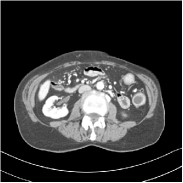

This special case of SUPER corresponds to the case where SUPER excludes the unsupervised regularizer, while only involves the data-fidelity and a supervised regularizer in the MBIR cost, i.e., β=0𝛽0\beta=0 and μ0𝜇0\mu\neq 0. In this case, the proposed SUPER model is similar to a generalized block coordinate descent-based network by replacing a simple denoising autoencoder [28, 29, 30] with a general CNN that forms our supervised regularizer. This SUPER is also similar to the plug-and-play ADMM-Net method except that the inputs to each supervised network are the preceding reconstructions, while plug-and-play ADMM-Net updates inputs to the network (denoiser) based on auxiliary variables in the ADMM algorithm. Here, we used μ=1×106𝜇1superscript106\mu=1\times 10^{6}, which worked well for the plug-and-play ADMM-Net method, for this special case of SUPER. Fig. 7 shows a comparison between plug-and-play ADMM-Net, SUPER without unsupervised regularizers (in both training and testing), and the full SUPER version with ULTRA regularization (β=5×103𝛽5superscript103\beta=5\times 10^{3}, μ=5×105𝜇5superscript105\mu=5\times 10^{5}). All these methods used WavResNet as their denoisers/supervised networks. In this example, SUPER with only a supervised regularizer (SUPER-WRN-β=0𝛽0\beta=0) outperforms the plug-and-play ADMM-Net (ADMM-Net (WRN)) by 1.6 HU RMSE and provides sharper image details. Comparing SUPER-WRN-β=0𝛽0\beta=0 and the full SUPER-WRN-ULTRA scheme, we observe that the latter provides a lower RMSE and higher contrast image features than the former that excludes the unsupervised component. This again shows the effect of the unsupervised ULTRA model (in capturing local image details better with a union of learned transforms) in the SUPER scheme.

Refer to captionADMM-Net (WRN)RMSE = 32.90 HURefer to captionADMM-Net (WRN)RMSE = 32.90 HU

Refer to captionSUPER-WRN-β=0𝛽0\beta=0RMSE = 31.32 HURefer to captionSUPER-WRN-β=0𝛽0\beta=0RMSE = 31.32 HU

Refer to caption SUPER-WRN-ULTRARMSE = 29.74 HURefer to caption SUPER-WRN-ULTRARMSE = 29.74 HU

Refer to caption ReferenceRefer to caption Reference

Figure 7: Reconstructed images of L192 slice 150 with WavResNet plugged ADMM-Net, SUPER-WRN-β=0𝛽0\beta=0 (both training and testing), and SUPER-WRN-ULTRA (β=5×103𝛽5superscript103\beta=5\times 10^{3} in both training and testing), respectively, shown with the reference image.